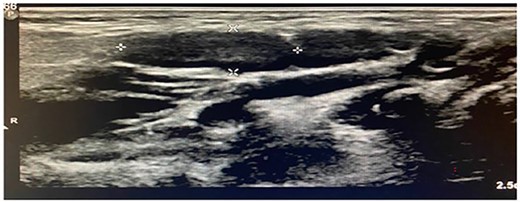

Imaging examination of the patient was done by performing CT and US. US Doppler showed a right dilated internal jugular vein (Fig. 2). The CT scan confirmed this finding, which suggested internal jugular vein phlebectasia (Fig. 3).